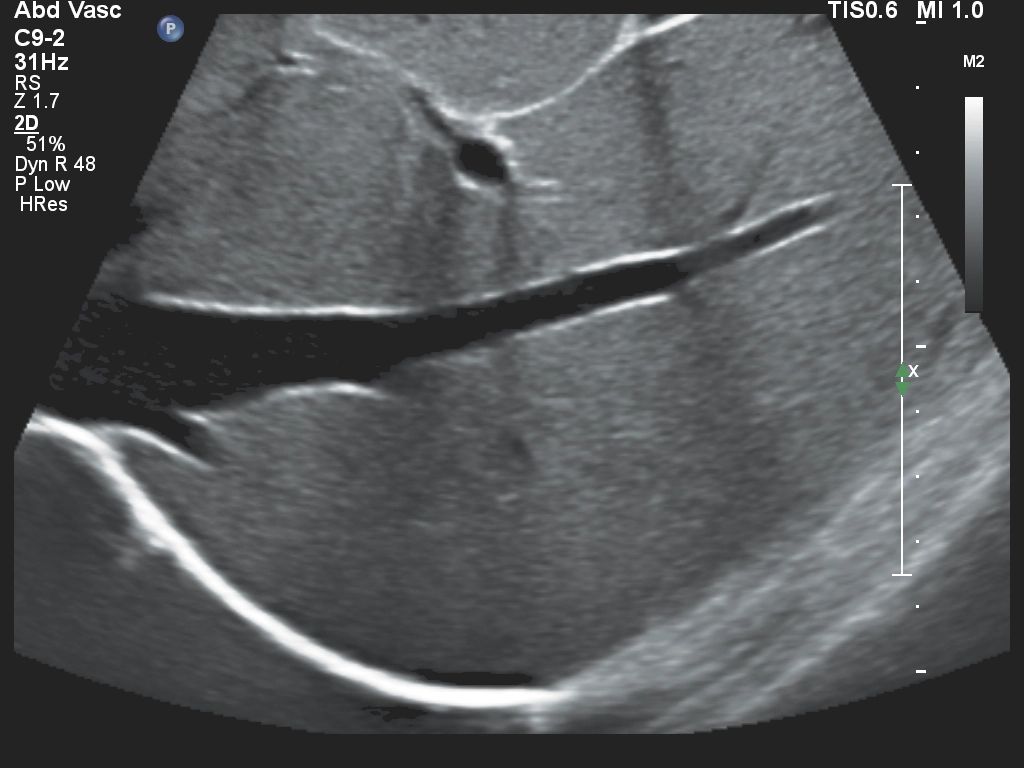

- Малые и поверхностные органы

- Micro Flow Imaging - возможность визуализации сосудов с низкой скоростью кровотока для точного анализа и оценки перфузии небольших сосудов

- Энергетический доплер CPA

- Функция Auto Doppler для исследования сосудов